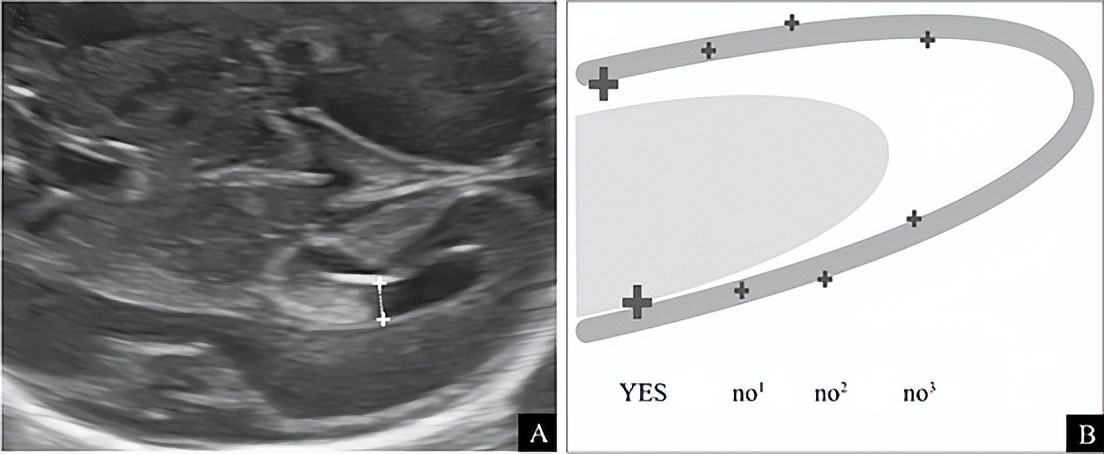

2)侧脑室宽度:是评价脑室系统最有效的方法。在侧脑室体部显示脉络膜丛,测量线垂直于侧脑室腔,游标置于侧脑室壁内侧进行测量(图5)。侧脑室在中孕和晚孕早期内径恒定,平均6~8 mm,并且整个孕期均应<10mm(推荐等级:C 级),当侧脑室宽度≥10mm 时,应引起注意。需强调的是:①脑室宽度在整个孕期可增加也可减小;②双侧脑室轻微不对称,但宽度均<10mm时属正常现象。

图5 A:侧脑室宽度测量:在脉络丛水平,测量游标置于侧脑室壁内侧缘;B:测量侧脑室时游标的正确位置,游标置于侧脑室内缘,测量垂直侧脑室最大宽度(YES)。

其他 no1、no2、no3 均为错误的测量方式